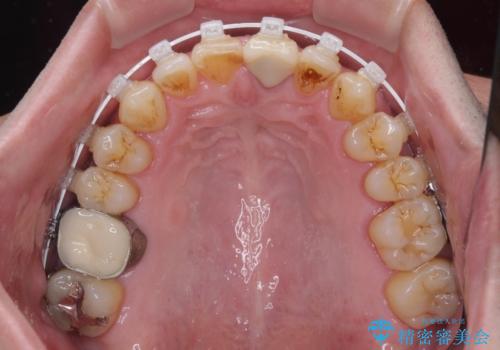

- 長年気になっていた口元を改善したいとのことで来院された患者様です。

外科手術を併用した矯正治療を検討するほどに隙間の空いた開咬と、顕著な叢生が認められました。

開咬の改善には、舌の突出癖改善のためにトレーニングを行いつつ、インビザラインでの矯正治療が大変有効ですが、上顎骨が下顎骨に対して前方位に位置しており、インビザライン単独で治療を行うよりは補助装置とワイヤー矯正で奥歯の咬み合わせを改善してから、開咬改善のためのインビザライン矯正治療を行うこととしました。

奥歯の銀歯は、土台の一部に抜歯が必要であったので、矯正治療の途中で抜歯してからオールセラミックブリッジによる補綴治療を行うこととしました。